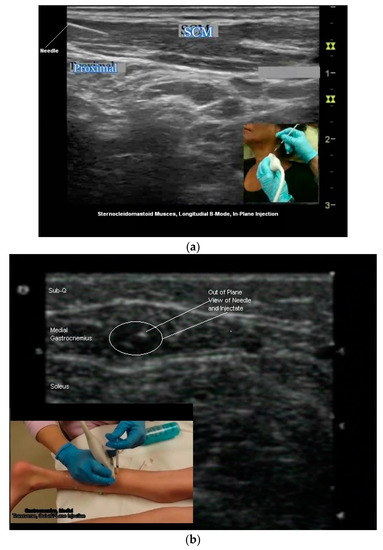

Figure 6.

(a) Long-axis B-mode US image, hand (palmar surface); (b) long-axis B-mode US image, anterior neck; (c) long-axis B-mode US image, flexor forearm.

Figure 7.

(a) Longitudinal B-mode US image, inplane injection; (b) transverse B-mode US image, out of plane injection medial gastrocnemius; (c) illustration, out of plane view of needle tip and shaft.

Two needle insertion techniques are utilized when performing US guided BoNT injections: Out of plane and in plane (Figure 6b,c and Figure 7a–c). There are advantages and limitations to each insertion technique. One technique may be superior to the other for a given patient or particular muscle/structure. Therefore clinicians should be familiar with both approaches [24,50,54].